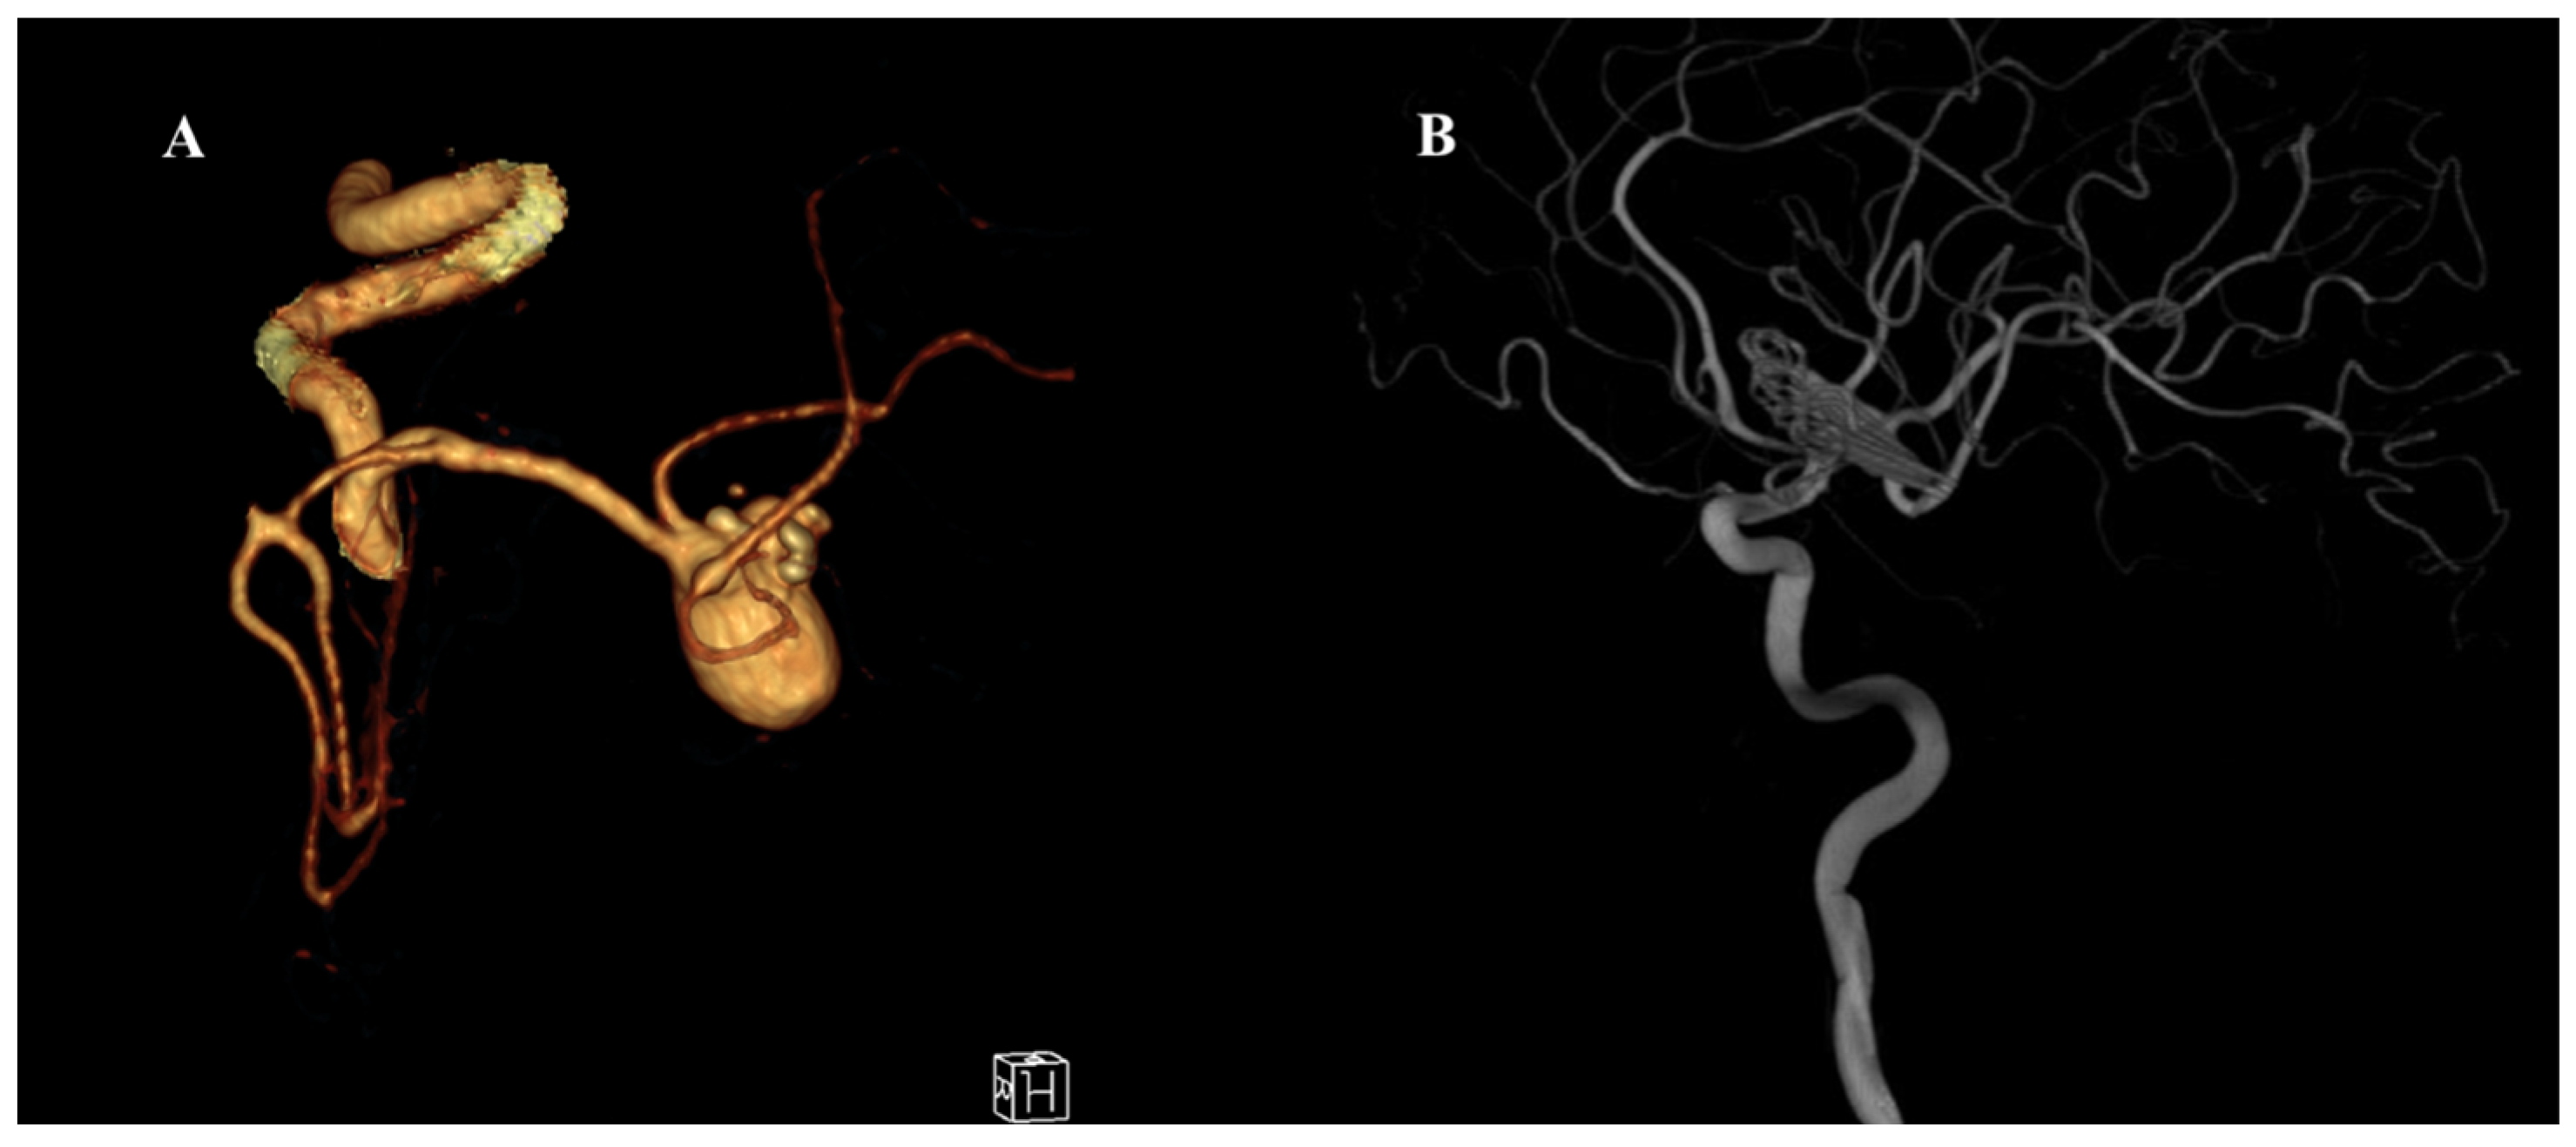

Figure 1. Preoperative and postoperative angiographic images of a giant middle cerebral artery (MCA) aneurysm. (A) Three-dimensional CT angiography reconstruction demonstrating a giant MCA bifurcation aneurysm with multilobulated morphology and complex neck anatomy. (B) Postoperative digital subtraction angiography (DSA) image showing complete occlusion of the aneurysm following surgical clipping using the picket-fence technique. The parent vessels and MCA branches remain patent without evidence of residual aneurysm or stenosis.